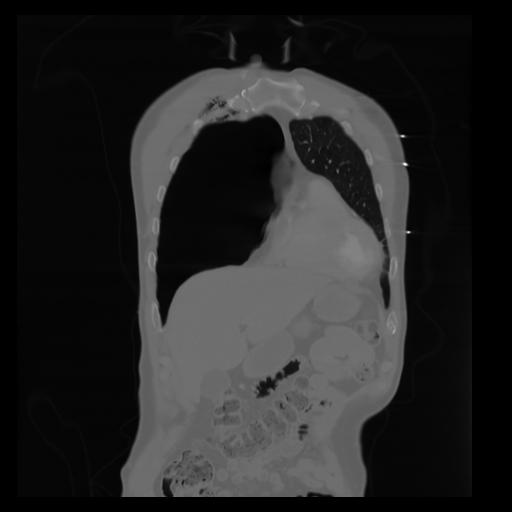

29 CUERPO,CE,Coronal,3.000,CUERPO,Coronal,